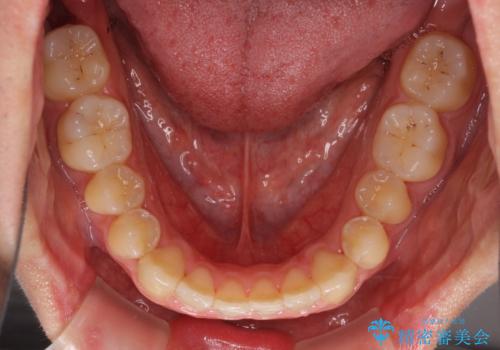

- 上下前歯のデコボコを気にして来院された患者様です。

叢生は軽微であり、費用を抑えて期間もあまりかけずに治療をしたいとのことで、インビザライン・ライトを用いて矯正治療を行うこととしました。